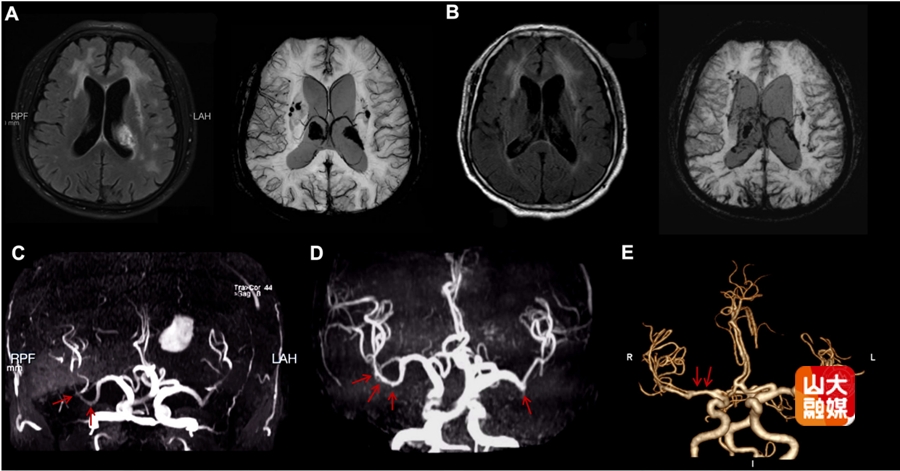

该团队在2026年1月份Stroke(中科院一区,IF = 8.9)杂志上报道了一例罕见的神经布鲁氏菌病相关脑血管病变。该研究通过动态影像学证据,首次完整展示了由布鲁氏菌感染引发的脑白质损害、脑出血及大脑中动脉串珠样扩张,经过抗感染治疗后呈现出动态改变。这一发现为感染相关脑血管病提供了全新的影像学表型,拓展了神经布鲁氏菌病的临床认知。齐鲁医院神经内科副研究员段若楠、医师高天宇为共同第一作者,赵玉英教授为通讯作者。